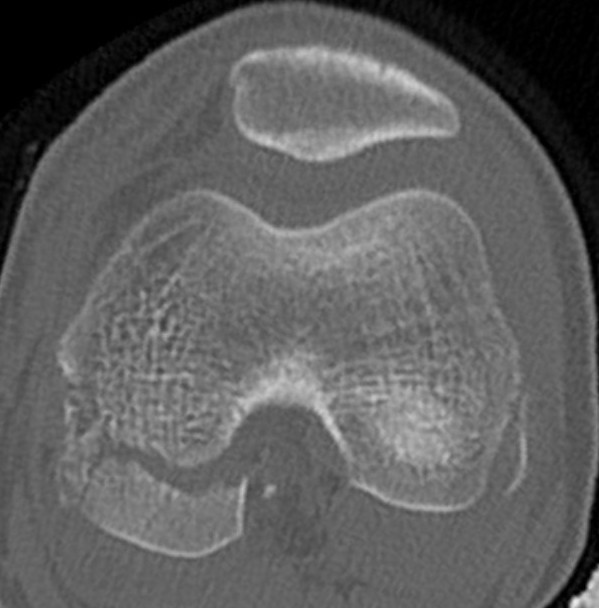

CT

Aids surgical planning

Medial Hoffa CT 1Medial Hoffa CT 2Medial Hoffa CT 3Medial Hoffa CT 4